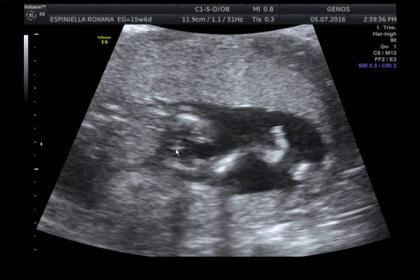

Last guesses! Today update and confirmation!!!!